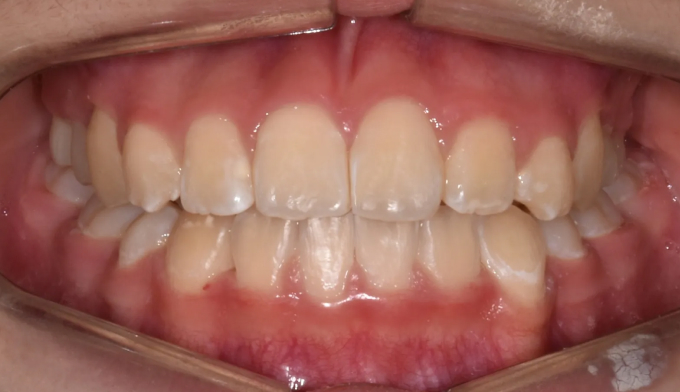

너무 늦은나이에 교정치과를 찾아서 아쉬운 경우입니다.

너무 좁은 위턱 공간으로 인해 치아의 맹출 순서가 어긋나버렸습니다.

이와 더불어 좁은 위턱 악궁은 얼굴 전체의 비대칭을 유발하고 있고, 아래턱의 과성장은 주걱턱 경향까지 보이고 있습니다.